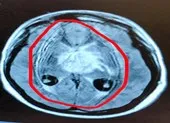

Khai thác bệnh sử, các bác sĩ nghi ngờ bệnh nhi có tổn thương thần kinh trung ương nên đã cho chỉ định chụp MRI não và phát hiện có khối u lớn nằm ở vùng sọ nền.

Hình ảnh MRI phát hiện khối u kích thước 27mm x 14mm  ở vị trí sọ hầu của bé gái 9 tuổi. Ảnh: BV cung cấp

Kích thước khối u khá lớn, vị trí tại sọ hầu có xâm lấn xoang hang. Đây là nguyên nhân chính dẫn đến tình trạng sức khỏe suy kiệt, ảnh hưởng thị lực và sự phát triển của bé. Hiện bé đã chuyển lên bệnh viện tuyến trên để được theo dõi và tiếp tục đều trị.